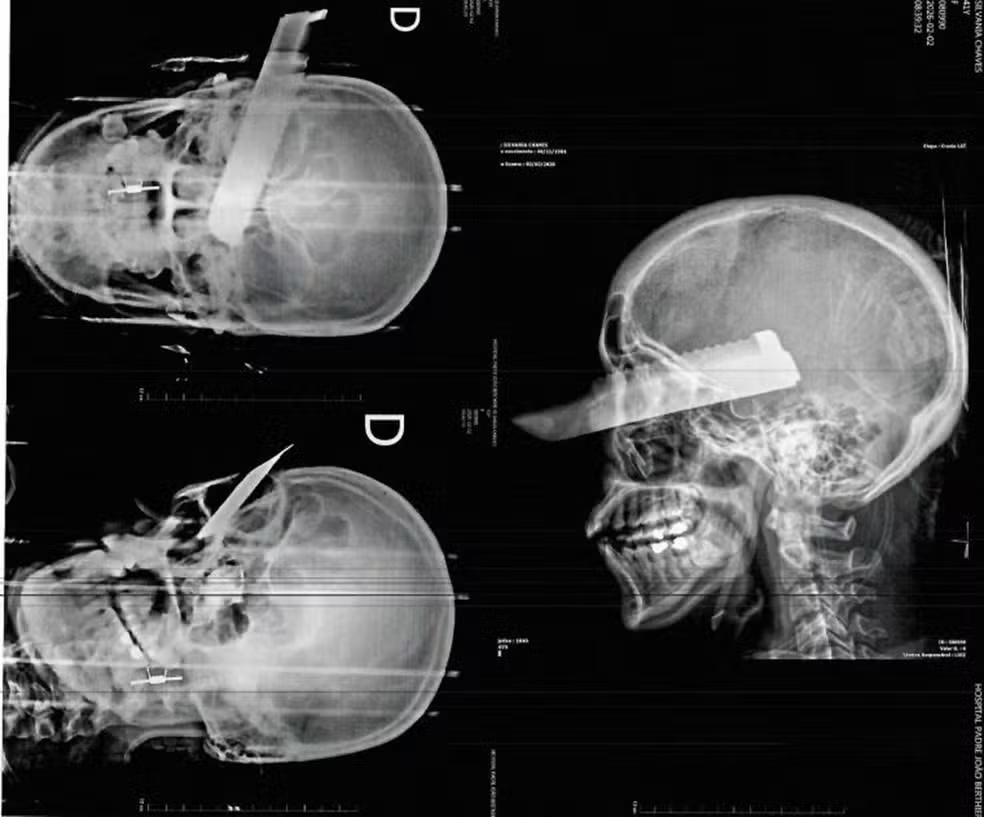

Após ser agredida, a mulher conseguiu deixar o local e pedir ajuda a vizinhos, sendo atendida pelo Corpo de Bombeiros e encaminhada ao Hospital Regional do Oeste, em Chapecó. Ela apresentava hematomas no rosto, no braço e na perna esquerda, além de uma lesão grave no olho direito, causada por uma facada desferida enquanto tentava escapar das agressões, conforme informou a Polícia Civil.